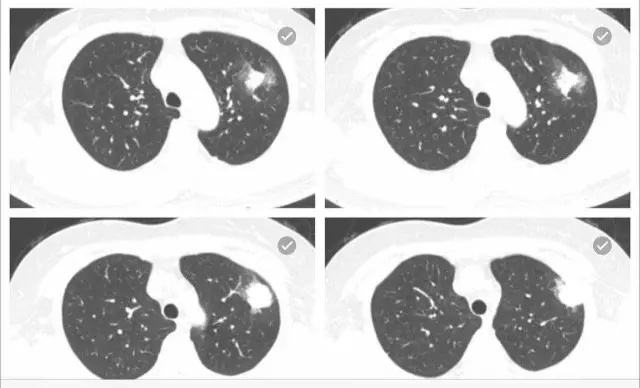

患者咳血胸痛一周。

肺部占位。

病变考虑为肿瘤或炎症,血象不高,肿瘤序列正常,结核试验阴性,ect阴性。请问贺主任意见?

左肺上叶尖段可见4.5*1.8cm的楔形实变病灶,尖端朝向肺门,周边可见浸润样实变。病灶中央可见低密度的无强化区,可见引流支气管;相邻胸膜可见增厚。会诊意见: 左肺上叶实变病灶,中央有液化坏死,考虑炎症性病变,霉菌、隐球菌或结核,请结合临床和治疗变化。供参考。建议最后提供原始轴位图像。

和缓医生结核实验阴性,白细胞8000多,有咳血。

病灶形态比较单一,不支持结核。但糖尿病患者结核可以有此表现。可以按照炎症治疗动态观察,三周。

没有糖尿病病史。谢谢贺教授,我们也诊断炎症,建议抗炎治疗两周后复查,胸外科考虑肿瘤,建议手术。

最好治疗观察。